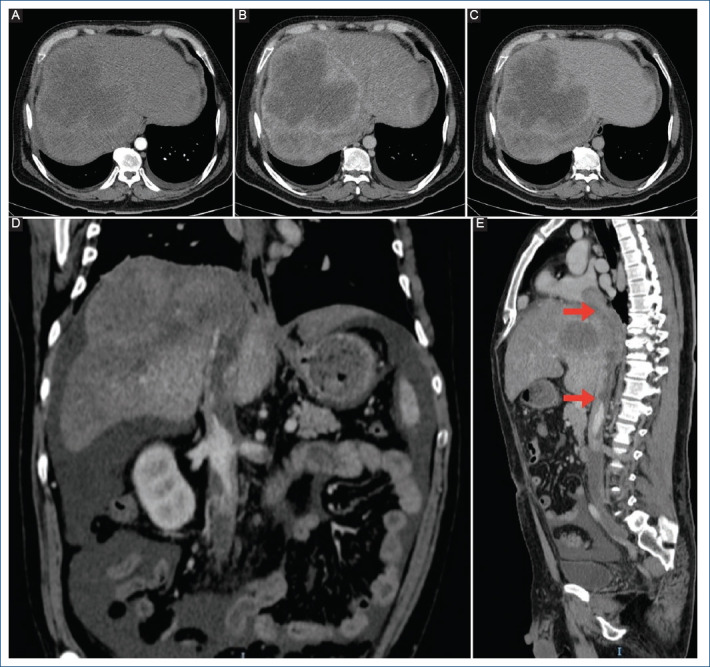

Hepatocellular carcinoma with inferior vena cava tumor thrombus extending into cardiac chambers: case report.